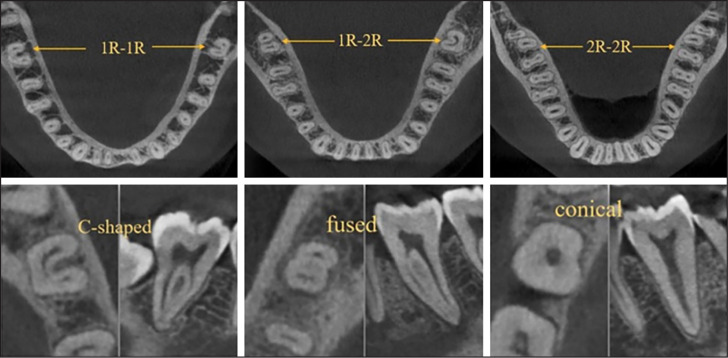

Objective: This study aimed to examine the mandible form features of the mandible, such as inter-second molar width, anteroposterior length, arch perimeter length, arch breadth, corpus height/width in the mandibular second molars (MnSM) region, and arch form, and the relation for the occasion of the 1-rooted/C-shaped.

Methods: The study analyzed cone-beam computed tomography images of 215 male and 215 female Turkish patients to determine the prevalence of 1-rooted and C-shaped MnSM. Mandibular dentoalveolar characteristics of individuals with bilateral (1R-1R group) and unilateral (1R-2R group) 1-rooted MnSM were examined and compared with those with bilateral 2-roots (2R-2R group) MnSM. Statistical tests were performed using Chi-square, one-way ANOVA, Tukey, and binary logistic regression analysis at the 5% significance level.

Results: The prevalence of 1-rooted and 1-rooted/C-shaped MnSM was 12.79% and 9.65%, respectively. Root fusion was more commonly present in females (p<0.05). In the 1R-1R group, the anteroposterior length was shorter than in the 2R-2R group (p<0.05). There was no difference between the groups for other features (p>0.05).

Conclusion: Although the study found a shorter anteroposterior length in the 1R-1R group, no feature was a predictive variable for 1-rooted/C-shaped MnSM.